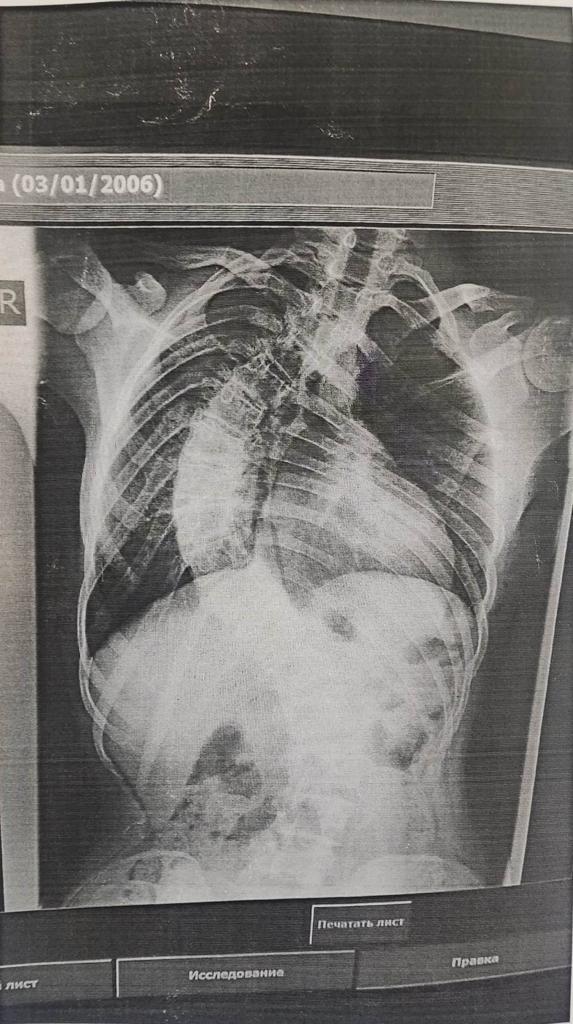

Victoria Pavlovich born on January 3, 2006.

After Surgery